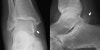

X-ray : 삼각골증후군(Os trigonal syndrome, Os trigonum, Posterior process fx)

X-ray 사진상으로 경계에 경화상이 보이면 오래된(진구성) 골절일 가능성이 큽니다.

무증상 환자 다수에서 후돌기 골절이 보이기 때문에 과연 이것이 통증의 원인인지 생각해 보아야 합니다.

잘 모르는 경우에는 골절로 판단하고 당황할 수 있습니다.